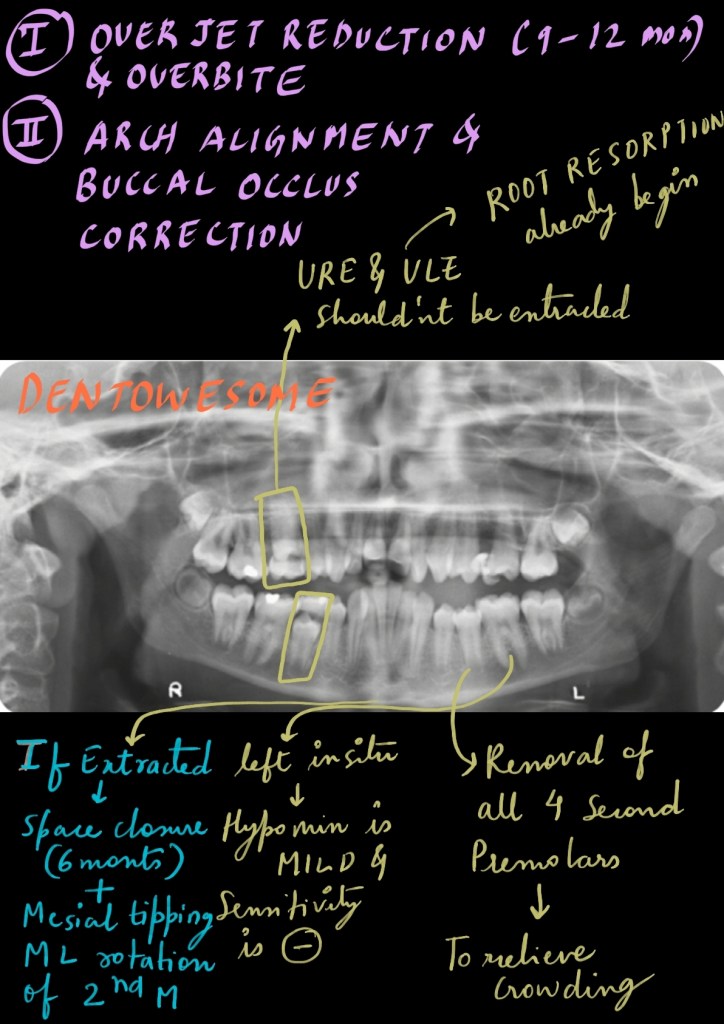

A 12-year-old female in the late mixed dentition with a class II division 1 incisor relationship on a moderate skeletal class II pattern with reduced MMPA. The malocclusion is complicated by:

• Increased overjet (12mm)

• Increased and complete overbite

• Crowding of both arches

• Mild molar–incisor hypomineralization.

Is removal of the URE, ULE and LRE indicated at this point? How would you treat this malocclusion? What are the potential orthodontic problems associated with removal of the first permanent molars? What prescription should be used during the fixed appliance phase?